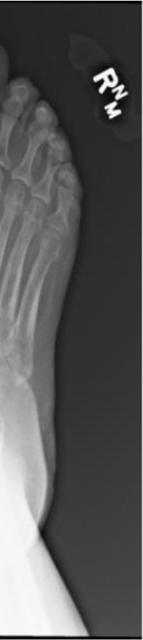

921 Charcot Neuroarthropathy of the Foot and Ankle in the Acute Setting: An Illustrative Case Report and Targeted Review

Kian Bagheri, Albert T. Anastasio, Alexandra Krez, Lauren Siewny, Samuel B. Adams

Duringthestudyperiodatotalof21participants comprising19residents(sixpostgraduateyear[PGY]1,